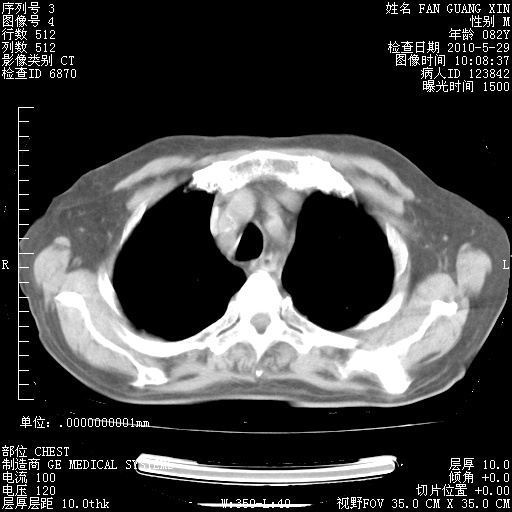

还需要哪些辅助检查?我们医院排除真菌感染没有任何检验方法,胸片好像能够排除肺部真菌感染。